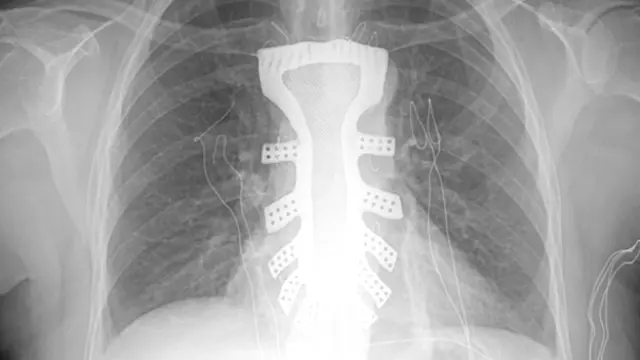

Médicos del Hospital Tangdu de Xian en China le han realizado a una mujer el primer implante de un esternón de titanio fabricado mediante una impresora 3D.

Una de los últimos tratamientos en los que se ha puesto en práctica esta técnica de fabricación ha tenido lugar en el Hospital Tangdu de Xian en China, donde una mujer de 54 años ha recibido el primer implante de un esternón de titanio hecho en una impresora 3D .

Sin embargo, este tratamiento dejaría expuesto el corazón de la paciente, lo que podía acarrearle infinidad de problemas de salud en el futuro. Estudiando a fondo el caso, los cirujanos llegaron a la conclusión de que podían reemplazar el esternón por una réplica exacta fabricada en titanio con una impresora 3D.

Para realizar la réplica del hueso, los médicos necesitaron analizar el esternón de otras mujeres de la misma edad y peso que la paciente, debido a que el tumor había desgastado mucho el original. Primero hicieron una copia en plástico para comprobar en el laboratorio que era adecuado, y una vez que el diseño fue aprobado se imprimió en titanio.

La intervención en la que los cirujanos realizaron el implante duró unas dos horas y media aproximadamente y fue todo un éxito. "La magia de la alta tecnología combinada con una atención médica excelente es lo que ha hecho que este milagro suceda", asegura la paciente.